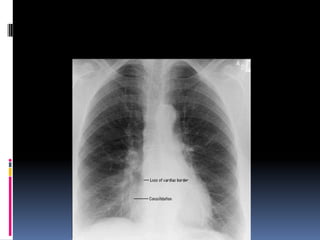

Lung fields

   Infiltrates

   Increased interstitial markings

   Masses

   Absence of normal margins

   Air bronchograms

   Increased vascularity